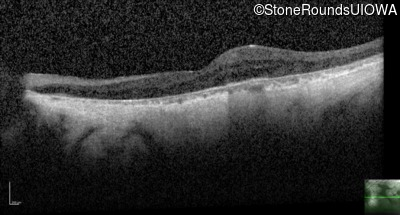

Age at visit: 67 years

This 54 year old man first experienced some reduction in his night vision at age 32. He had been treated with chloroquine for malaria for two years in his early 20s.

XL Choroideremia CHM Duplication Exons 6-8   XL